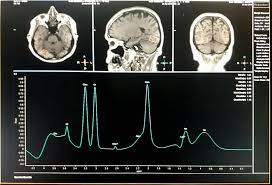

ESPECTROSCOPIA POR RM: O QUE É, QUANDO INDICAR E COMO INTERPRETAR

A espectroscopia por ressonância magnética (RM) é uma extensão da imagem convencional por RM que permite analisar o perfil químico dos tecidos. Em vez de apenas mostrar imagens anatômicas, ela revela informações sobre o metabolismo celular, sendo essencial para identificar alterações metabólicas precoces, principalmente no cérebro.

Os resultados da espectroscopia são exibidos em forma de espectro, com picos representando diferentes metabólitos. Os mais comuns são:

- NAA (N-acetil aspartato): marcador neuronal. Redução indica dano ou perda neuronal.

- Colina: associada à membrana celular. Aumento pode indicar proliferação celular ou tumor.

- Creatina: relacionada ao metabolismo energético. Serve como referência estável.

- Lactato: sinal de hipóxia ou necrose.